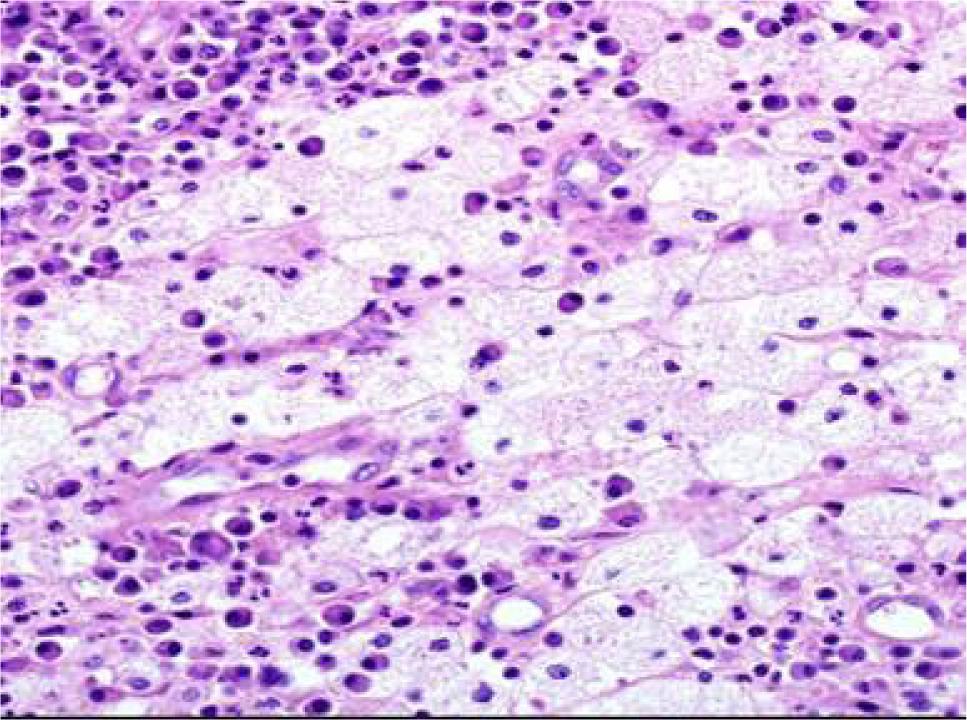

Figure 2: Photomicrograph image showing the renal parenchyma infiltrated with dense inflammation and foam cells on low magnification, suggestive of XGP on H&E staining.

Figure 3: Photomicrograph image showing foam (xanthoma) cells and lymphoplasmacytic inflammation on H&E staining in XGP patient on high magnification.

XGP is a relatively rare subtype of chronic pyelonephritis with varying occurrences, which range between 0.6% and 1% as reported in literature (1). XGP is usually diffused (involving most of the kidney), and focal variant is less common. All age groups may be affected, but it is more commonly spotted in middle-age and elderly patients. XGP has been more commonly reported in females (11). Our study too observed that XGP is more common in females as compared to males. All the patients had unilateral presentation, as bilateral presentation is rarely encountered (2). Obstruction of the urinary tract and recurrent urinary tract infection (UTI) are common in XGP (1). A study conducted in India reported that nephrolithiasis was observed in 90% of XGP patients (12). Similarly, in our study nephrolithiasis was observed in nine (60%) patients. Diabetes mellitus, urinary stasis because of obstructive pathologies, renal neoplastic lesions, and immunocompromised attributes predispose patients to XGP (13,14). In the present study, diabetes was diagnosed in six (40%) patients and none of our patients was on immunosuppressive medications or had underlying malignancy. Varying clinical presentations have been observed in different studies. All the patients had abdominal pain on presentation, which is similar to most of the published series (7,12,14). In a recent study, pyonephrosis and perinephric abscess were observed in 25.0% and 7.5% patients, respectively (12), whereas in our study, three (20%) patients had pyonephrosis and three had perinephric collection. In a study conducted in Turkey, leukocytosis was observed in one (7.7%) patient, pyuria was diagnosed in six (46.1) patients, and 46.1% patients were anemic (15). Korkes et al. (5) analyzed 41 patients of XGP, in which anemia, pyuria, and leukocytosis were reported in 63%, 57.6%, and 41% of cases, respectively. In our study 11 (73.3%) patients were anemic, leucocystosis was diagnosed in 9 (60%), and all the patients had pyuria. In a study conducted by Kundu et al. (12), XGP was diffused in 31 (77.5%) patients and focal in 9 (22.5%) cases whereas in our study, diffused XGP was observed in 11 (73.3%) patients, which was similar to their study. Moreover, they observed biopsy diagnosis of XGP in 23 (57.5%) patients, 10 (25.0%) patients had pyonephrosis with XGP, 3 (7.5%) had XGP with diabetic nodular glomerulosclerosis, and 1 patient had renal cell carcinoma with concomitant XGP(12). In our study, pyonephrosis with XGP was noted in three patients whereas another three had perinephric collection. Diabetic glomerulosclerosis with XGP was observed in one of the six diabetic patients in our study, and none of our patients had neoplastic lesions. XGP has been divided into three stages: stage I is nephric XGP, which is confined to the renal parenchyma; stage II is perinephric XGP, having involvement of the anterior perirenal fascia, or Gerota’s fascia; and stage III is paranephric XGP, having involvement of the pararenal space and retroperitoneal structures (16). In the present study, 12 patients had stage I disease and 3 patients had stage II disease. Histopathologic examination of XGP determined an admixture of lipid-laden foamy macrophages with infiltration of varying mixtures of inflammatory cells along with fibrotic changes and cholesterol deposition. We too observed most of these changes in our specimens.